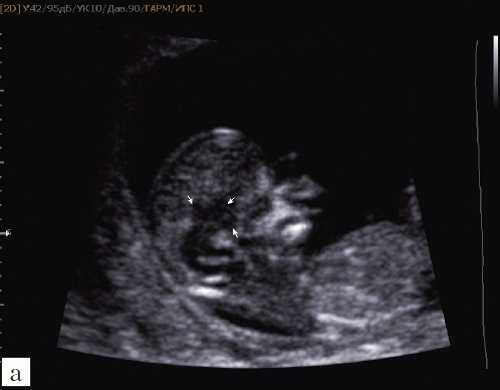

а) На эхограмме:

1 - ствол мозга;

2 - интракраниальное пространство, или IV желудочек;

3 - большая цистерна головного мозга;

4 - воротниковое пространство.

б) Вид "осьминожки":

- красный цвет - диэнцефалон (таламус), со стволом мозга (верхняя ножка) и IV желудочком (нижняя ножка);

- желтый цвет - большая цистерна головного мозга;

- синий цвет - воротниковое пространство.